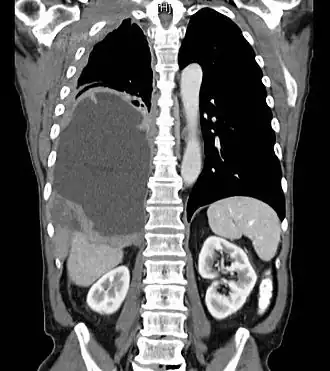

Même si le mésothéliome peut être dépisté par une simple radiographie du thorax, l'examen de référence est le scanner thoracique[8], l'IRM pouvant constituer une alternative[9]. La tomographie par émission de positons permet de faire le bilan d'extension[10].

Le scanner thoraco-abdomino-pelvien est aujourd'hui[Quand ?] l'examen morphologique de référence pour le diagnostic, le bilan d'extension et la surveillance du mésothéliome péritonéal. Il ne permet cependant que de dépister les lésions de plus de 5 mm et il sous-estime largement l'extension intrapéritonéale de la maladie[47].